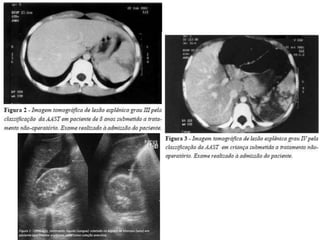

TRAUMA ESPLÊNICO

Conduta não-cirúrgica

UTI por 48-72h/ Repouso absoluto/ Cateter

nasogástrico  Medidas seriadas Ht (se queda,

recomenda-se nova TC de abdome) e Avaliação

clínica (exame abdominal frequente) 

Normalidade: Transferência para Unidade

intermediária/ Caminhar/ Iniciar dieta

Conduta cirúrgica (Laparotomia exploradora)

Estabilidade hemodinâmica com sinais de irritação

peritoneal, instabilidade hemodinâmica com LPD ou

FAST positivos, lesões graus IV e V (AAST) e

coagulopatia.